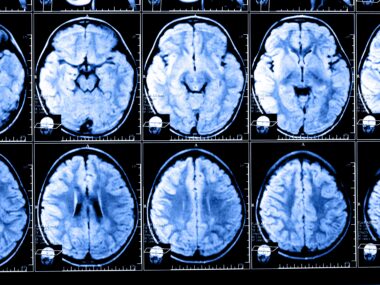

A paramagnetic rim lesion, or PRL, is a spot of chronic, inflammatory demyelination in the brain. PRLs are defined by a central core of pronounced demyelination, surrounded by a “rim” of iron-laden immune cells (microglia and macrophages), which has a characteristic appearance on MRI brain scans. The prognostic and diagnostic utility of PRLs is a subject of ongoing research, but remains incompletely understood.